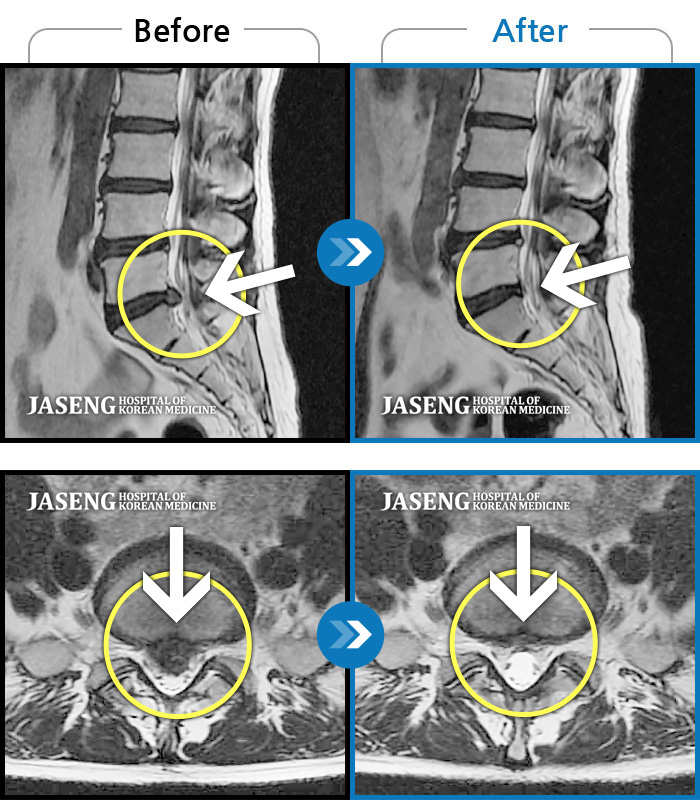

No.53 조회수 1,634 2021.10.08

No.52 조회수 86 2021.09.30